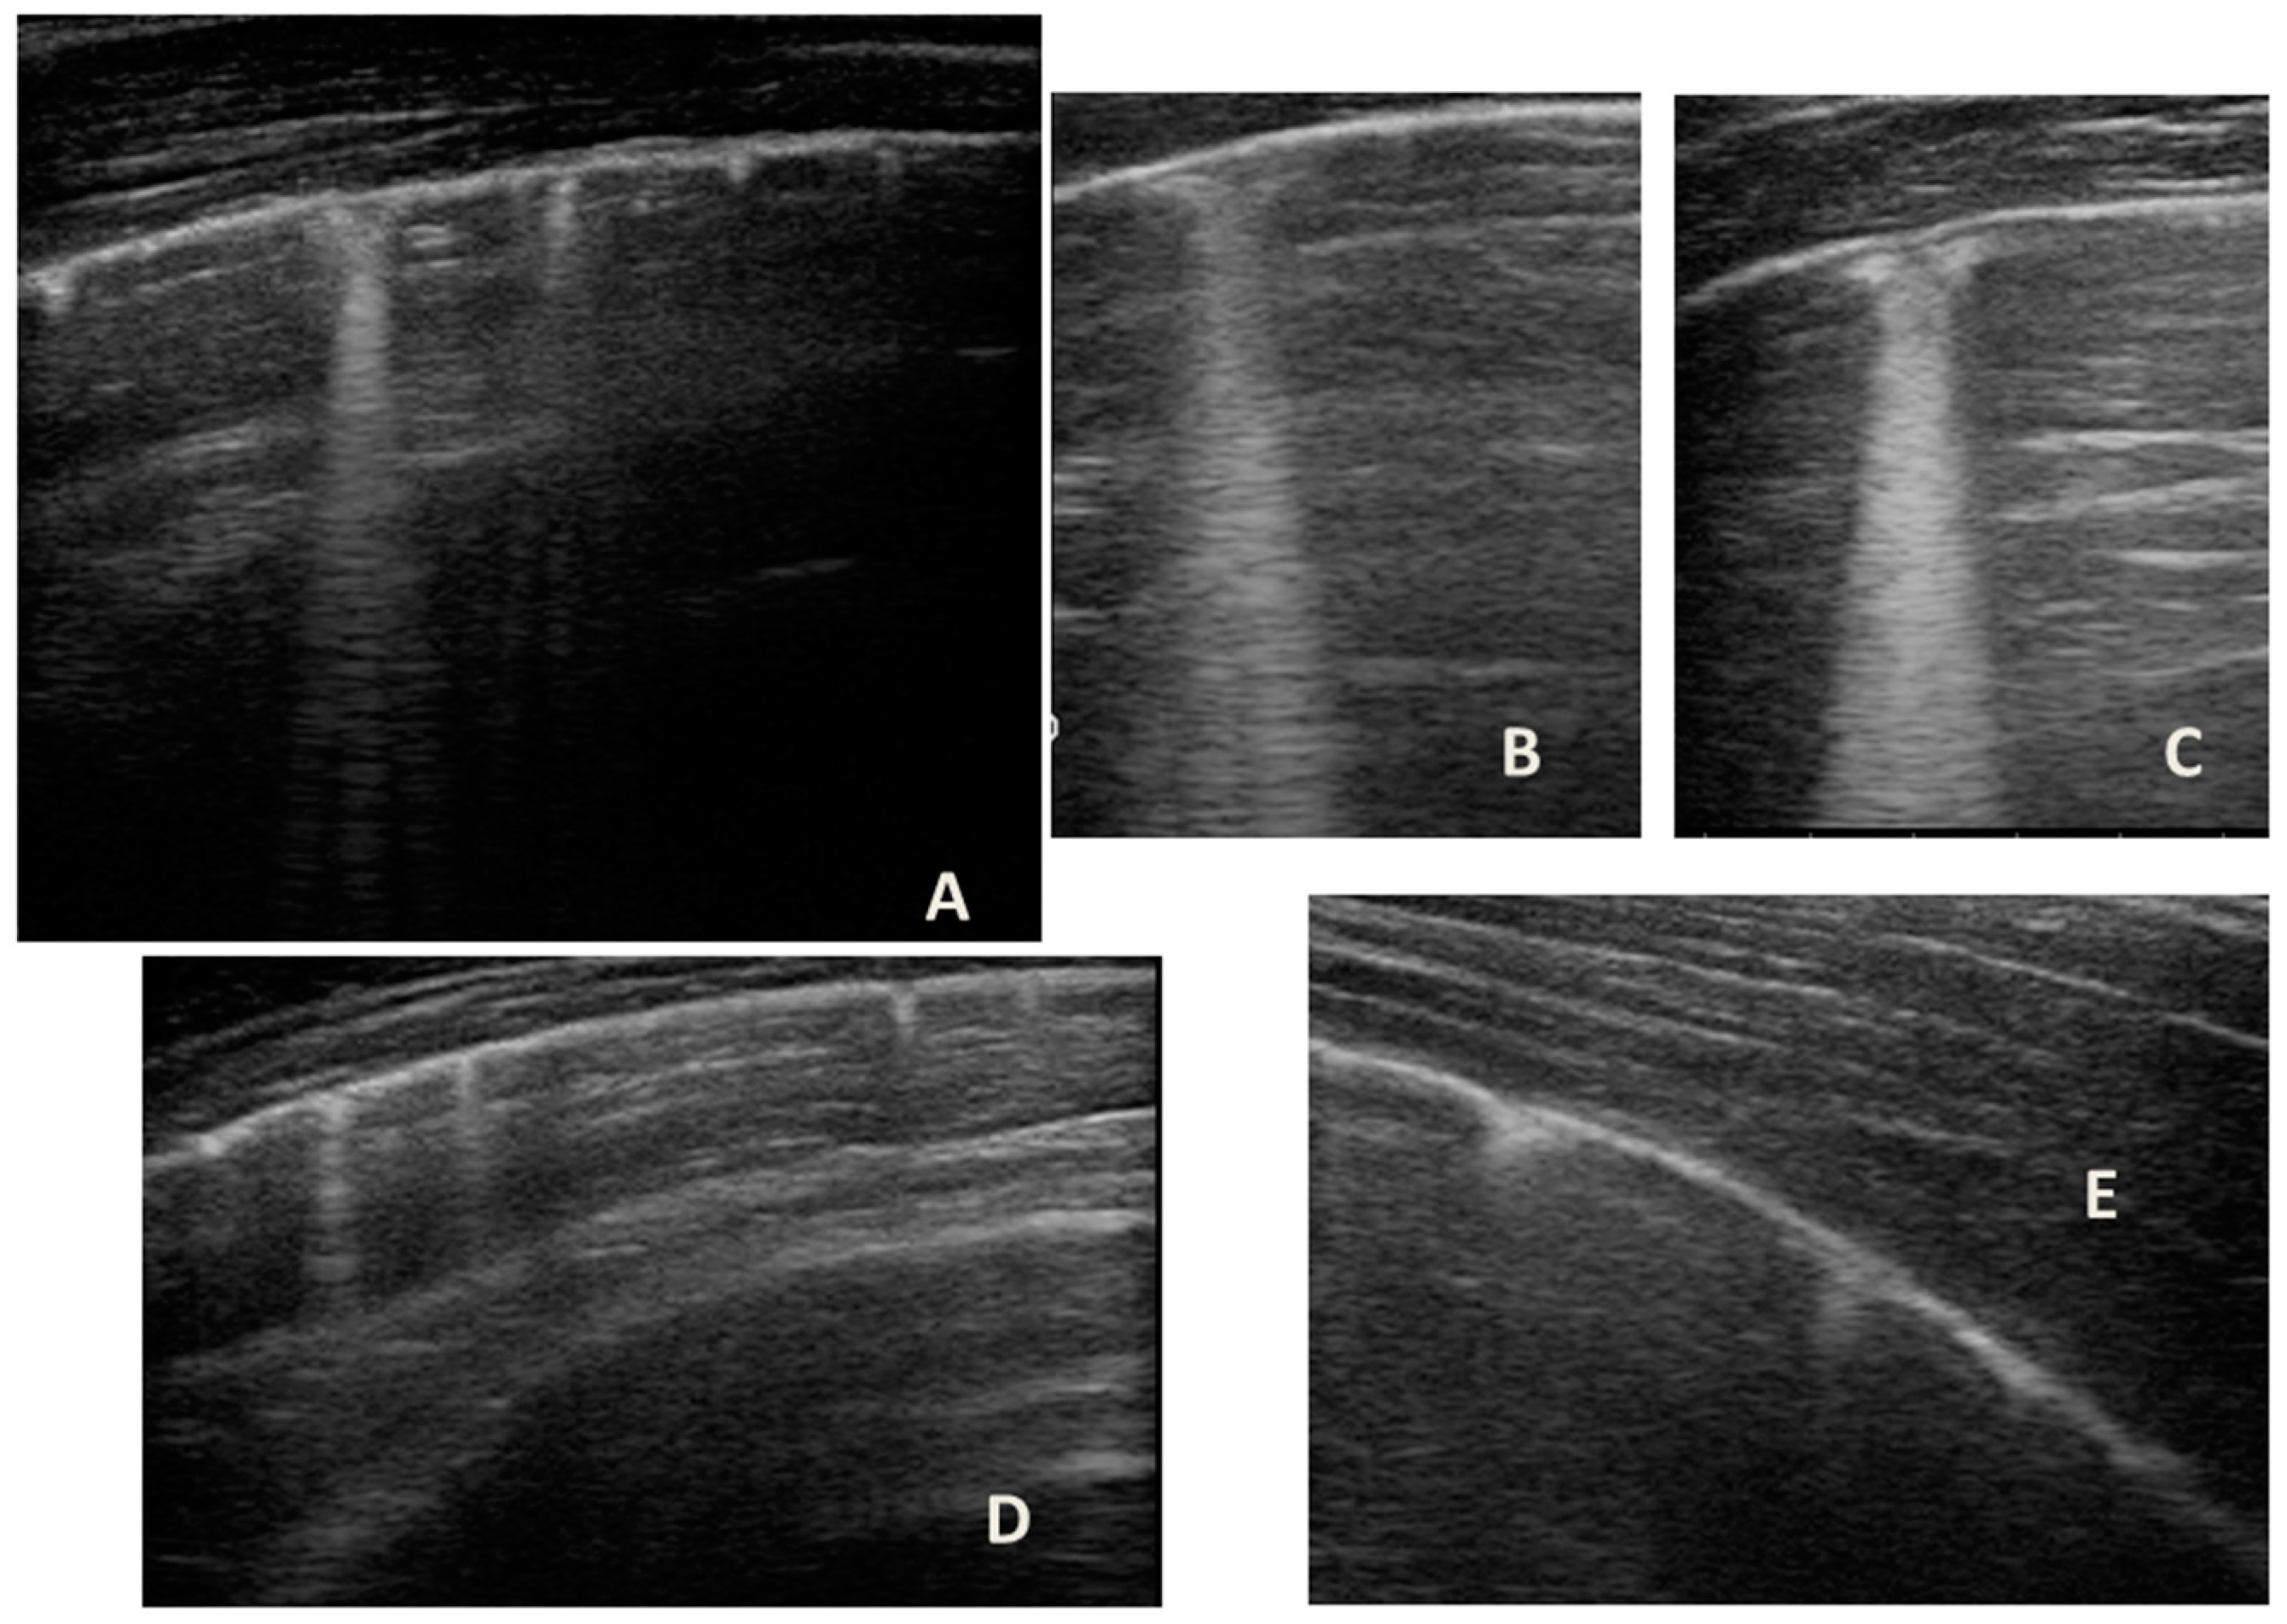

At our hospital, together with the clinical evaluation, we performed a lung ultrasound, which showed the presence of two areas of moderate lung atelectasis, in the right anterior mid-apical and in the left anterior paracardiac site, respectively, associated with sonographic interstitial syndrome (SIS) (Figure 1). LUS excluded the presence of inflammatory/infectious consolidations.

Figure 1.

Grayscale lung ultrasound examination shows: (A): on the right anterior field, mainly in the mid-apical area, consolidation of atelectasis origin (arrow) with static air bronchograms (punctate), and parallel to each other (arrowheads), associated with sonographic interstitial syndrome (SIS), represented by coalescent vertical artefacts or B-lines (asterisks); (B): on the left paracardiac site, consolidation of about 2.5–3 cm of atelectasis nature (arrow) with static air bronchograms (punctate) (arrowheads), associated with sonographic interstitial syndrome (SIS), represented by coalescent vertical artefacts or B-lines (asterisks).

The lung ultrasound follow-up showed complete resolution of the areas of atelectasis after 4 weeks from the start of background therapy, whereas the long vertical artifacts and irregularities of the pleural line persisted.

In our cases (Table 1), particularly in the first three cases—children with asthma not controlled due to an inadequate preventive therapy for age, phenotype, and severity of the clinical picture [1,2]—LUS was highly positive (Figure 1, Figure 3 and Figure 5). It showed the presence of lung atelectasis, which resolved slowly after weeks of therapy of the acute attack and the beginning of adequate preventive therapy. On the contrary, in case 4 and 5—children with asthma well controlled by adequate preventive therapy—LUS was not highly positive (Figure 6 and Figure 7). In fact, it did not show large atelectasis, but a slight SIS in case 4, and a SIS suggestive of viral infection of the small airways in case 5 [14,15].